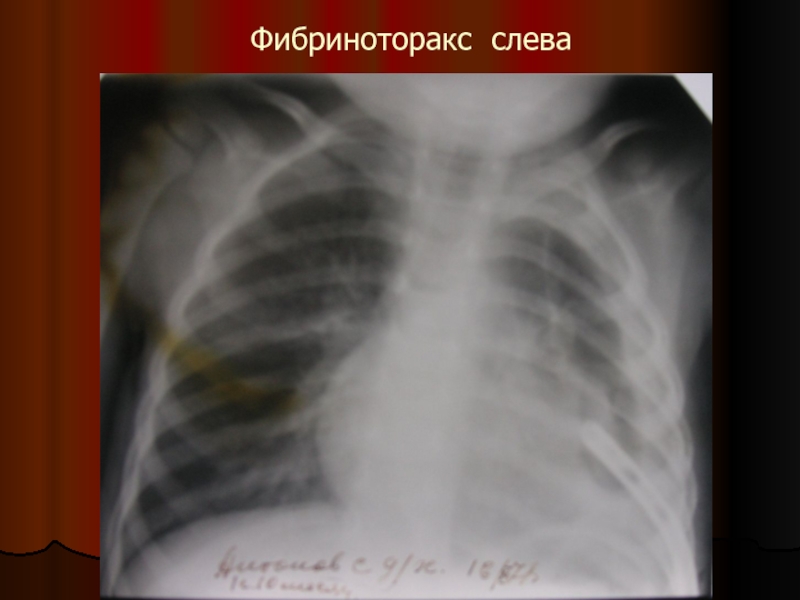

Слайд 50При позднем поступлении ребенка активная аспирация не всегда приводит к расправлению

легкого, что обусловлено его ригидностью из-за окутывающих фибринозных наложений (фибриноторакс). В таком случае прибегают к «поднаркозному» раздуванию легкого

Слайд 51Фибриноторакс слева